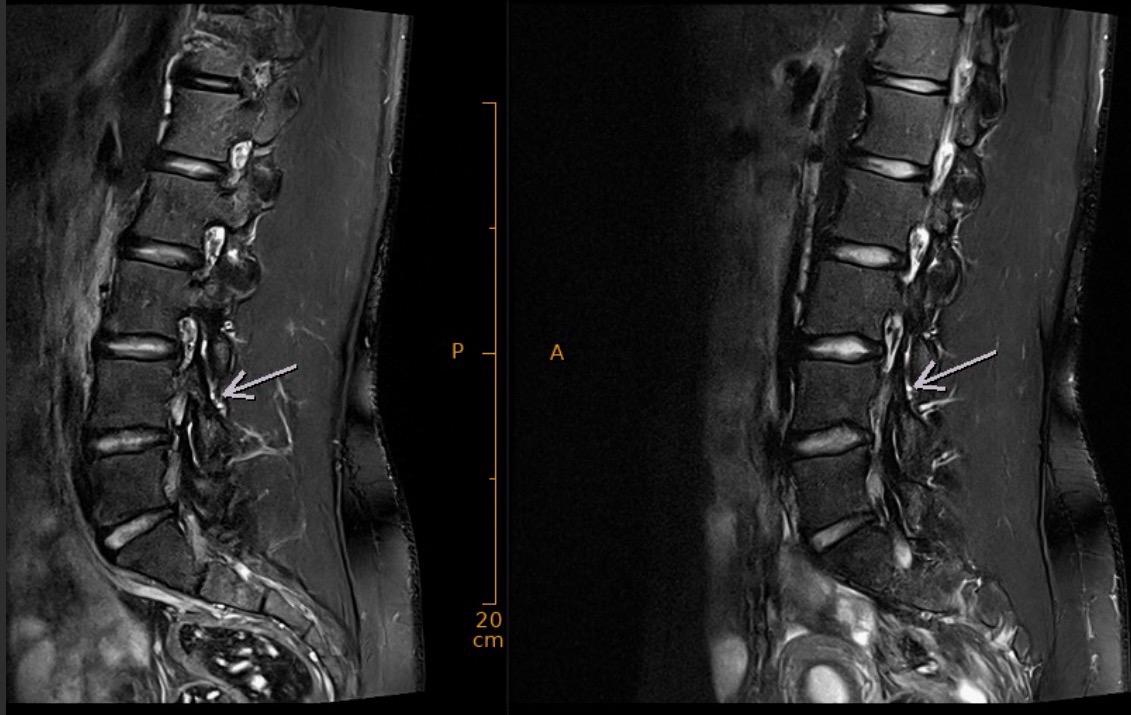

Depuis des tests physiques effectués mi-octobre à Macolin, Justine Herzog doit composer avec des douleurs au bas du dos. « Ces douleurs m’empêchent de m’entraîner normalement dans les parcours et ont freiné ma préparation automnale, notamment durant un camp de Levi (Finlande), où j’ai dû interrompre totalement l’entraînement, puis finalement renoncer à deux autres stages sur neige, explique Justine Herzog. Une IRM réalisée début novembre a mis en évidence une inflammation associée à une forte tonicité musculaire, ainsi qu’une protrusion discale exerçant une pression sur les nerfs et provoquant douleurs et gênes fonctionnelles, » explique encore l’athlète du cadre C de Swiss-Ski.

IRM Justine Herzog